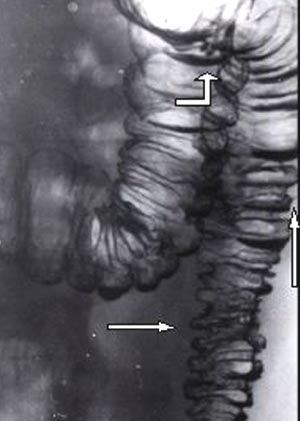

Дивертикулярная болезнь толстой кишки.

Рис. 2. Сочетание преддивертикулярной стадии в нисходящей кишке (горизонтальная стрелка), стадии интрамуральных дивертикулов (вертикальная стрелка) и полных дивертикулов фигурная стрелка).

Предоставил Дементьев Е.З.

Радиология-практика 2004 2: 48-56